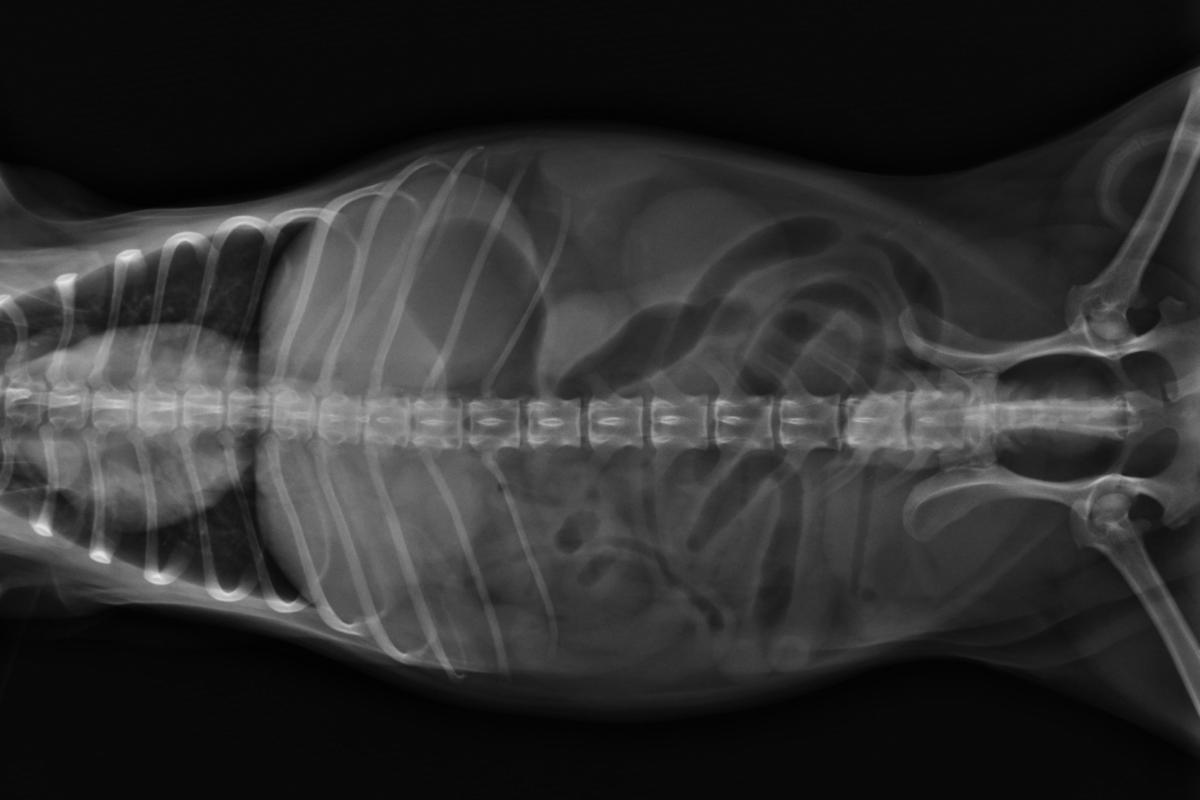

No obstante, el veterinario no puede diagnosticar definitivamente la presencia de una inflamación intestinal si no realiza alguna prueba complementaria que la confirme. Para ello, lo más habitual es recurrir a un análisis coprológico, es decir, el estudio de las heces, su contenido y su consistencia, así como llevar a cabo alguna técnica de diagnostico por imagen que permita ver la apariencia del tracto digestivo. En este sentido, lo más utilizado es la ecografía abdominal, pues es una técnica poco invasiva, totalmente inocua para el animal y que aporta muchísima información sobre el estado intestinal del peludo.